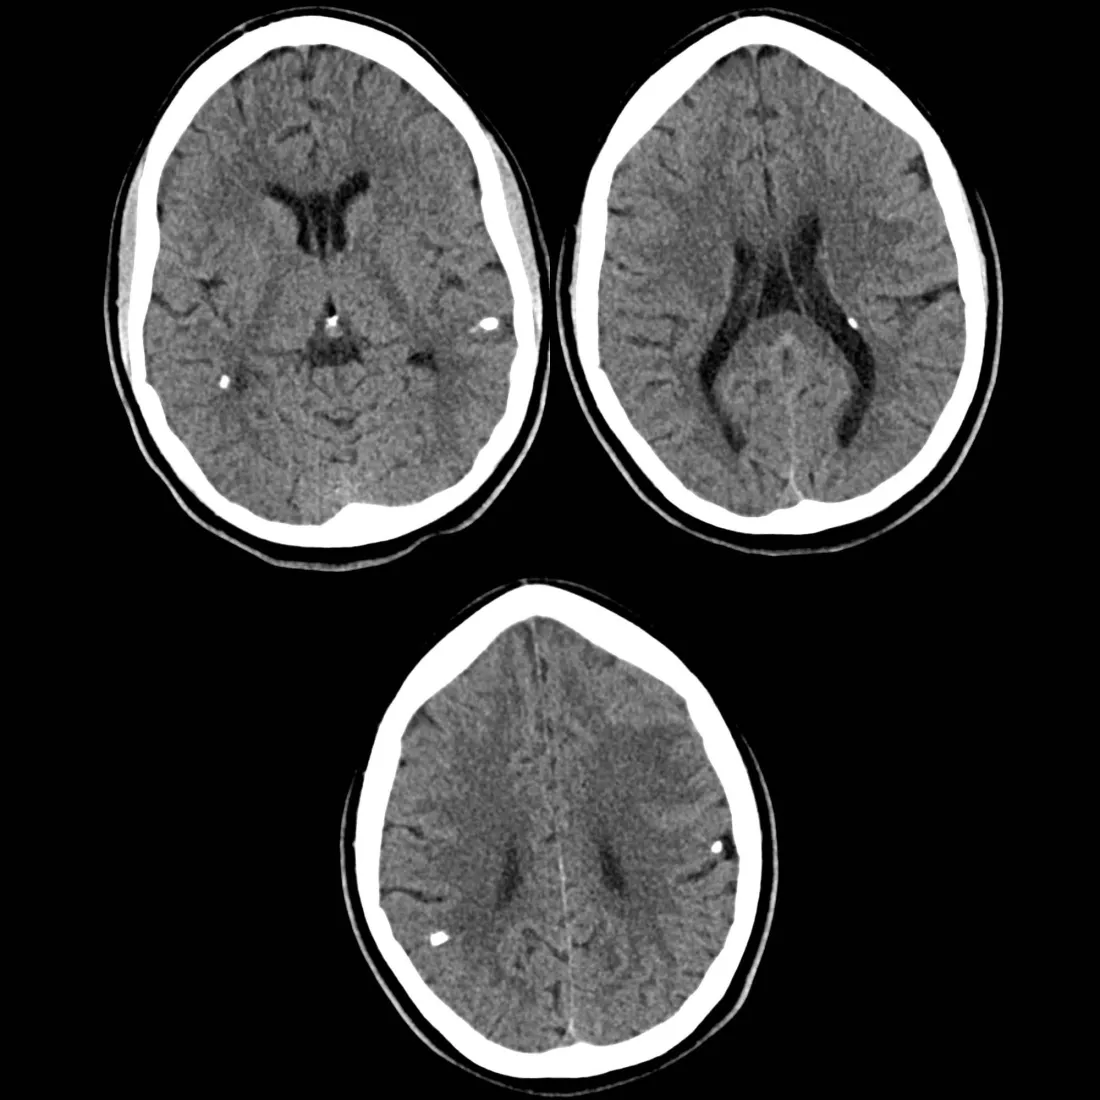

Selepas disahkan positif HIV & Toksoensefalitis, dia nangis meraung-raung

Di sebalik gaji yang lumayan, dia bagaimanapun disahkan menghidap Toksoensefalitis (bisul/keradangan otak) serta jangkitan kelamin. Sepanjang dirawat di hospital, lelaki itu benar-benar menyesal dengan jalan hidup yang dipilihnya dan dilihat sentiasa membaca Al-Quran. Tidak lama kemudian, dia akhirnya kembali kepada Sang Pencipta.